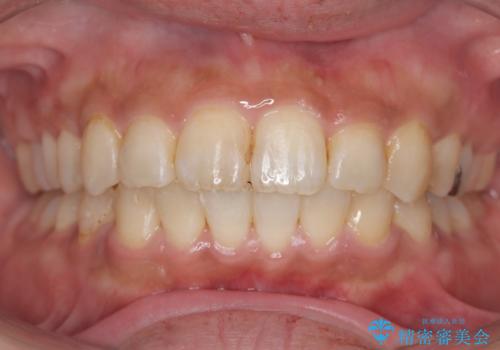

ワイヤー矯正(審美装置)非抜歯 治療期間:1年8か月

一日に物を口にする回数が多い方はマウスピース矯正における推奨装着時間を守ることや、その都度歯磨きをすることが難しいため、ワイヤー矯正での治療となりました。